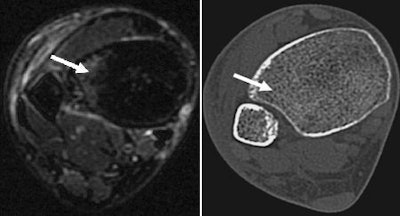

| Transaxial images at the tibial pilon of the right ankle joint in a 40-year-old woman with acute ankle trauma. T2-weighted short-tau inversion recovery (STIR) MR image (left) shows subtle bone marrow lesion in the lateral aspect of the anterior tibial pilon (arrow). Weighted-average image simulating single-energy CT (right) shows no fracture (arrow). |